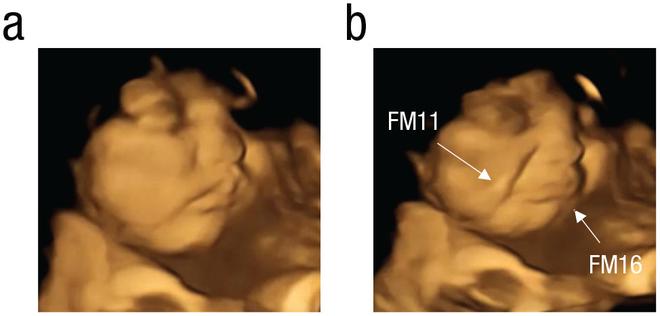

The researchers analysed 4D ultrasound scans of 100 pregnant women who are 32 to 36 weeks along in their pregnancies from northeast England. They found that the foetuses exposed to carrot flavour showed ‘lip-corner puller’ or laughter-face’. While those exposed to kale flavour showed ‘upper-lip raiser’, ‘lower-lip depressor’ or ‘cry-face’.